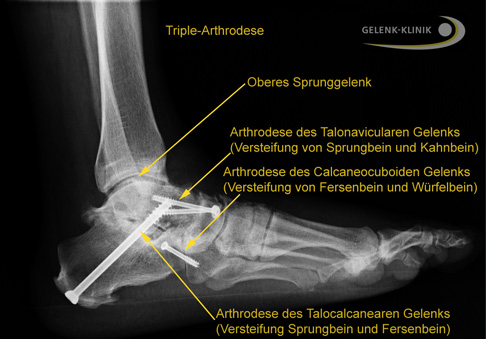

Triple-Arthrodese: Versteifung des unteren Sprunggelenks

Eine der häufigsten Ursachen für den Hohlfuß ist die CMT-Erkrankung (Charcot-Marie-Tooth-Erkrankung).

Dabei ist die Triple-Arthrodese des unteren Sprunggelenks bei der CMT-Erkrankung ein letztes Mittel der operativen Stabilisierung.

Meist kann diese Erkrankung konservativ behandelt werden. Es gibt jedoch schnell fortschreitende Formen der CMT-Erkrankung. Bei diesen tritt als Folge eine progrediente Muskelschwäche und damit eine ausgeprägte Hohlfußfehlstellung auf. Das führt zu starken, degenerativen Veränderungen an Sprunggelenk und Fußwurzelgelenken.

Die Stabilisierung des Fußlängsgewölbes durch eine Triple-Arthrodese kann in diesem Fall die Funktion des Sprunggelenks erhalten. Bei dieser Operation wird der Rückfuß durch eine Versteifung des unteren Sprunggelenks stabilisiert und das Fußlängsgewölbe in der gewünschten Position fixiert. Dadurch reduziert sich die Überlastung des oberen Sprunggelenks und der Verschleiß wird gestoppt. Die Beweglichkeit des oberen Sprunggelenkes bleibt nach Triple-Arthrodese vollständig erhalten.